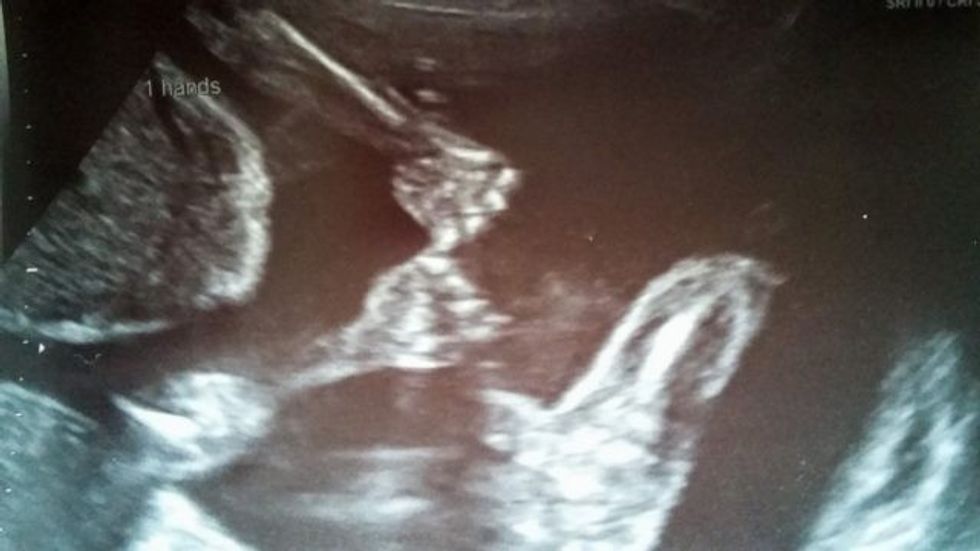

Binjakët identikë mbijetojnë duke mbajtur njëri-tjetrin për dore (Foto)

Hayley Lampshire u tmerrua kur mori vesh se shtatzënia e saj rrezikohej, pasi binjakët e saj kishin një problem që hasej rrallë, por që mund të çonte në vdekjen e foshnjave.

Foshnjat në bark ndanin një qese të lëngut amniotik, ndërsa ishin të domosdoshme dy, përcjell GSH.

Doktorët kishin paralajmëruar se nëse njëri prej tyre lëvizte rreth mitrës mund të mbytej ose të mbyste tjetrin.

Mirëpo, ata thyen çdo parashikim dhe arritën të mbijetonin në barkun e nënës duke mbajtur njëri-tjetrin për dore. Sot, vogëlushët gëzojnë shëndet të plotë.